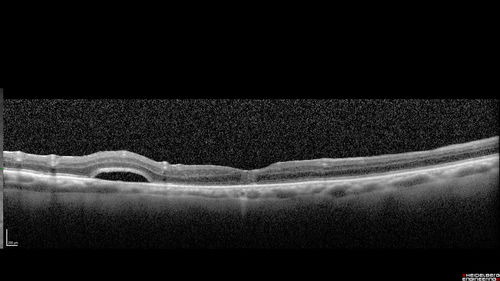

Macular Hole with Limited Retinal Detachment - 3 months post-op

87 year old female with decreased vision in the left eye for 2 months.  VA 5/200.  Initial three images are pre-op.  Then there is 3 months 6 months and 9 months post-op scans.  VA improved at 1 year to 20/50.  Surgery was done with Brilliant Blue.